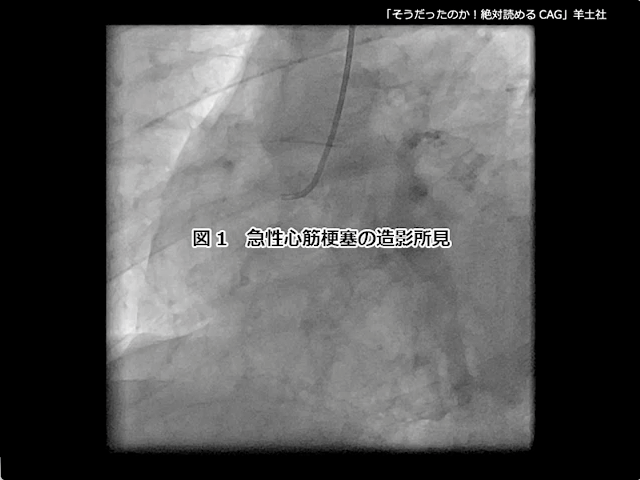

第5章-1 急性冠症候群の造影所見